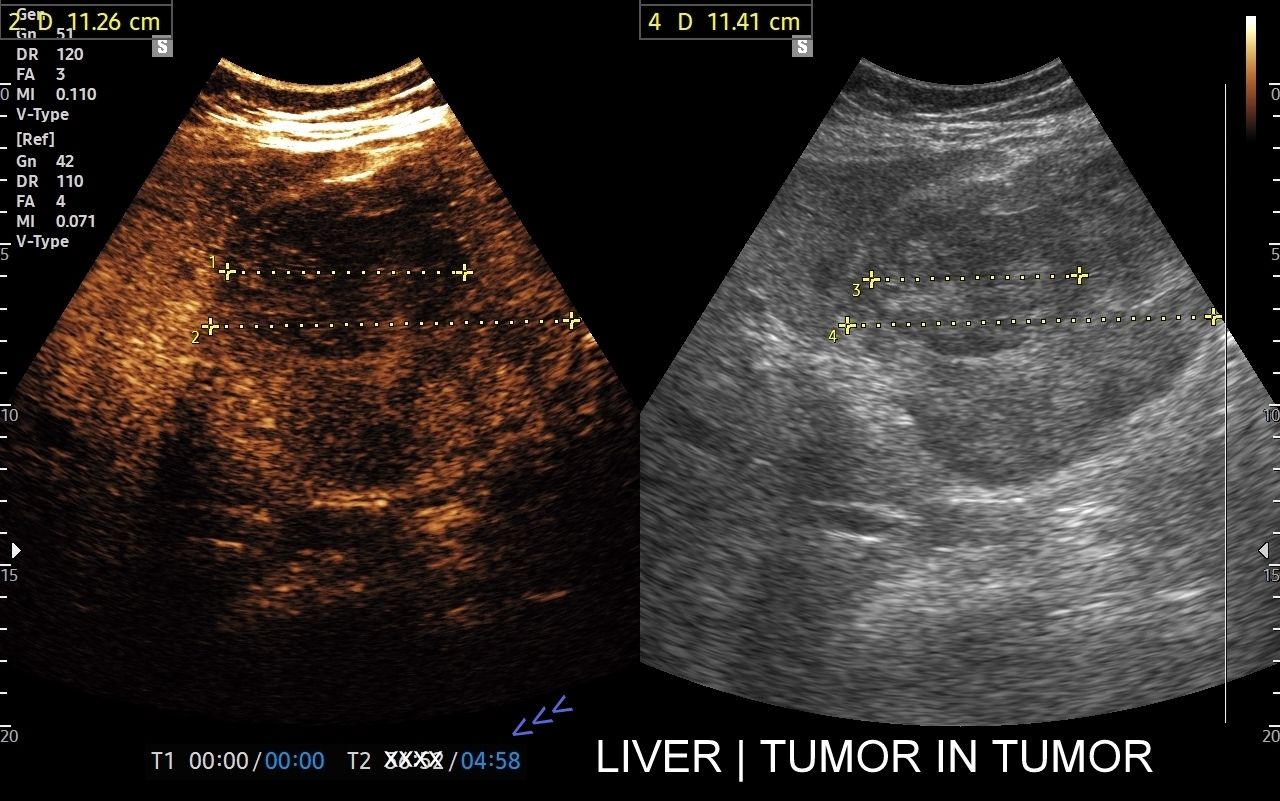

Badanie USG z kontrastem najczęściej wykorzystuje się do oceny zmian ogniskowych w wątrobie, potocznie nazywanych guzami wątroby, z których wiele ma na tyle specyficzny obraz mikrounaczynienia w obrazowaniu CEUS, że możliwe jest uniknięcie konieczności badania obciążającymi metodami TK lub MRI. Badanie CEUS w przeważającej większości pozwala odpowiedzieć, czy zmiana ogniskowa wątroby ma cechy złośliwe czy łagodne. Dodatkowo CEUS jest pomocny do wykrywania przerzutów do wątroby pochodzących z nowotworów w innej lokalizacji. W przypadku przerzutów o wielkości mniejszej niż 1 cm CEUS ma większą czułość aniżeli badanie TK.

CEUS jest badaniem w czasie rzeczywistym pozostającym pod kontrolą operatora, podczas którego możliwe jest wykonanie próby czynnościowej oraz natychmiastowe powtórzenie całego badania w razie konieczności. Możliwości takich nie dają ani TK ani MRI. Dodatkowo CEUS cechuje się o wiele większą rozdzielczością czasową w porównaniu do wspomnianych metod, co umożliwia uwidocznienie wczesnej fazy tętniczej unaczynienia podejrzanej onkologicznie zmiany ogniskowej w wątrobie i jej lepszą charakterystykę.